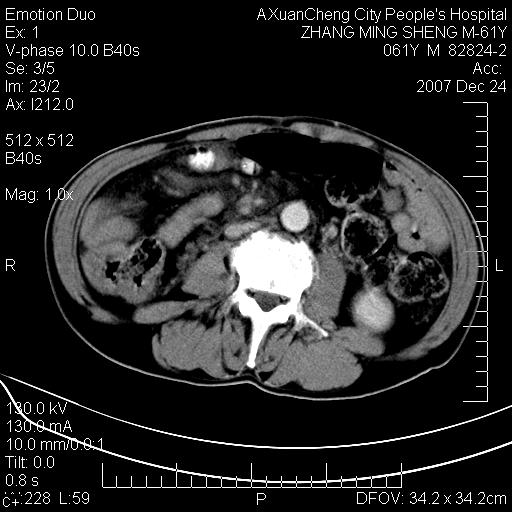

标题: CT11031:M61Y,胰腺占位

大家侃侃门静脉和胆管系统怎么回事,肝内转移?

胰腺癌肝转移

2,肝内多发结节状低密度占位,伴门脉及肠系膜上v栓子形成.考虑a;门脉及肠系膜上v血栓后肝改变.b;弥漫型肝癌伴门脉及肠系膜癌栓.

肝硬化,门脉高压,脾肿大;弥漫性肝癌,肝内、门脉、腹膜后淋巴结转移,肝内外胆管扩张,胰头区占位,建议mr检查

胰腺癌伴肝内转移;门脉、肠系膜上v癌栓形成。

考虑为:胰腺癌伴肝脏转移、腹膜后淋巴结转移,门静脉及肠系膜上静脉瘤栓形成。

胰体尾癌伴肝内转移,门静脉及肠系膜上静脉瘤栓形成.